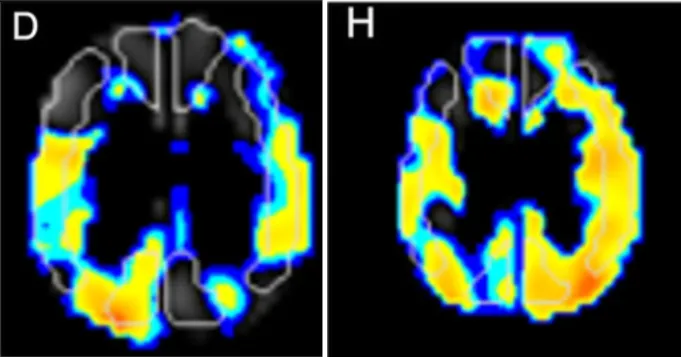

术前:SPECT成像显示左MCA和PCA区域的CVR降低(图D)

术后:SPECT成像显示MCA和PCA区域的CVR显著改善(图H)